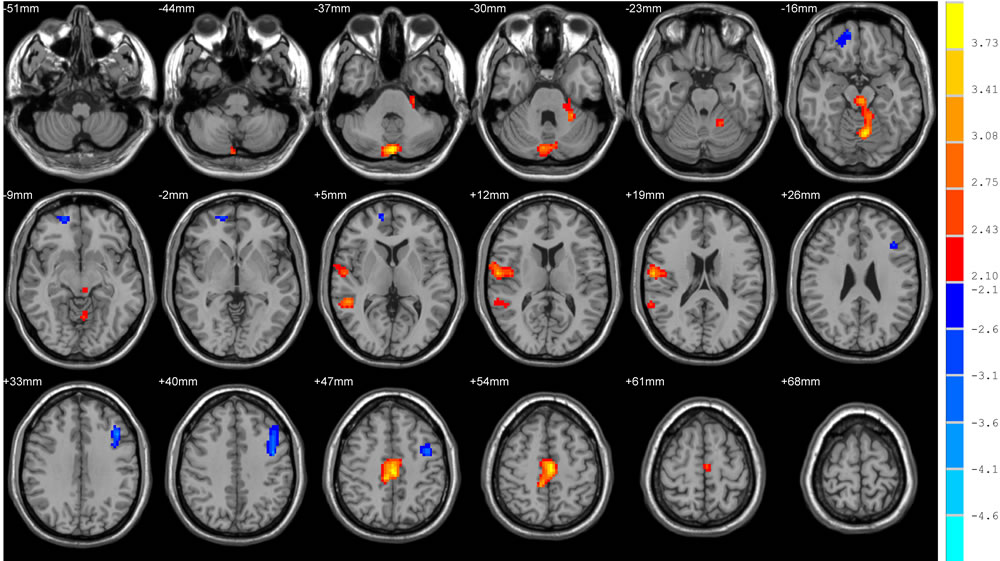

After controlling for the depression and anxiety scores, there was no significant difference between the two groups for the ReHo and FA of the ROIs at baseline. The Lilliefors goodness-of-fit test of all RS-fMRI data showed that the P-value of most voxels was greater than 0.05, we consider that the sample were normally distributed. In the HC group, we found no significant difference of ReHo values by performing voxel-based paired t tests between t1 and t2. In the CT group voxel-based paired t tests, we found significant increases of ReHo in the posterior lobe of the cerebellum and the anterior lobe of the cerebellum, and significant decreases in the right orbitofrontal area, right middle and superior temporal gyrus, right subcentral area (between the insula and post/precentral gyrus), and the left dorsolateral prefrontal cortex and precentral gynus (Table 3 and Figure 1). For the DTI analysis, FA values have been compared in predefined regions according to the ICBM DTI-81 atlas. This atlas contains 50 regions, and differences were found in 3 out of the 50 regions in the CT group without FDR corrections. The regions were the fornix, the left superior fronto-occipital fasciculus (SFOF), and the right SFOF (P < 0.05) (Table 4). However the corrections results showed that they were not significant after FDR corrections. In the HC group, we found no significant difference of FA values when performing paired t tests between t1 and t2.

Figure 1: Brain areas with significant changes of ReHo values after chemotherapy in paired t tests. Warm and cool colors indicate significantly decreased and increased ReHo values at P < 0.05 (AlphaSim corrected, cluster size>1458 mm3, spatial smoothness = 4, rmm = 4).